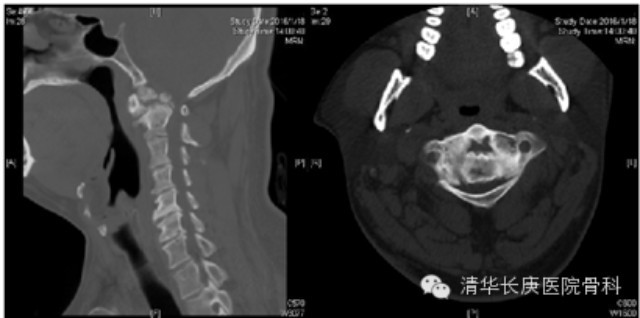

清华长庚医院2月21日电(骨科 宋飞)近日,北京清华长庚医院骨科脊柱专业组收治一名复杂上颈椎畸形患者,先天性枢椎齿状突发育不良伴寰枢椎脱位,出现进行性加重的脊髓损害表现(图1)。骨科主任肖嵩华教授主刀为患者施行联合前后路手术:前路经口减压松解、减压、齿状突切除,后路寰枢椎椎弓根钉内固定植骨融合。

图1、术前CT:齿突发育不良,增生硬化,高位颈脊髓严重受压,后伸不能复位